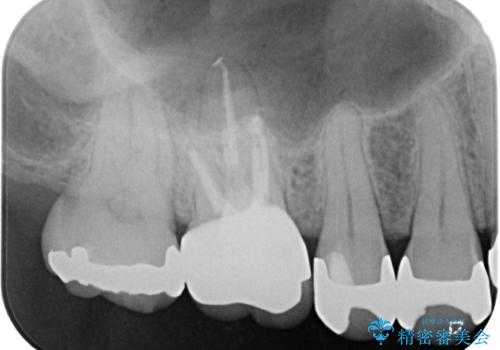

治療途中の奥歯 オールセラミッククラウンでのむし歯治療

- 近医にて治療を行っていたものの、痛みがなかなか引かないとのことで転院されてきた患者様です。

上下で接触しないように削られていたため、日常生活で痛みを感じることはありませんでしたが、歯を叩くと痛みを感じる状態でした。

前医ではラバーダムの装着をされていない状態で根管治療を行っていたようで、その他の器具や処置も無菌的環境下であったとは考えにくいため、それが痛みがなかなか引かない原因の一つであると考えられました。

根管治療後に痛みの消失を確認し、オールセラミッククラウンにて補綴治療を行うこととしました。

初回の根管治療時に仮歯を装着しましたが、仮歯を介して食事などを行っても痛みは感じなくなっており、その後は速やかに補綴治療を行いました。